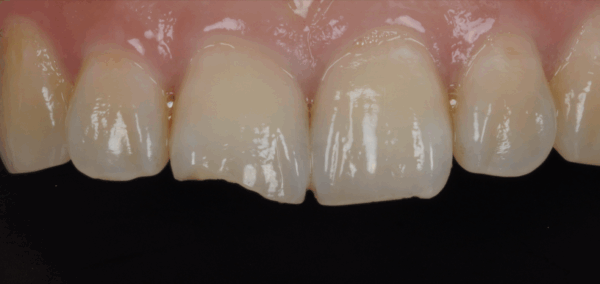

門牙斷掉怎麼辦?牙醫解析門斷裂的原因、常見治療方式與真實案例,包括美學樹脂、陶瓷貼片與全瓷冠修復。

門牙補過反覆變黑?不一定要做貼片或牙套。美學樹脂可以在保留齒質的前提下改善黑邊與外觀。本文用真實案例帶你了解判斷邏輯、適合對象與治療流程。